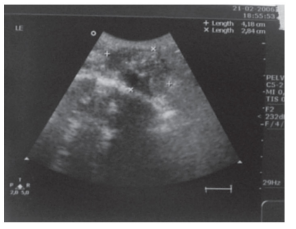

Uma mulher de 53 anos, eutireoidea, tem queixa de

discreto aumento do volume cervical há 1 ano. Realizou uma

ultrassonografia de tireoide que evidenciou nódulo medindo 3,5 ×

2,7 cm, conforme evidenciado na imagem.

Acerca do TIRADS e da PAAF, deve-se considerar, respectivamente: